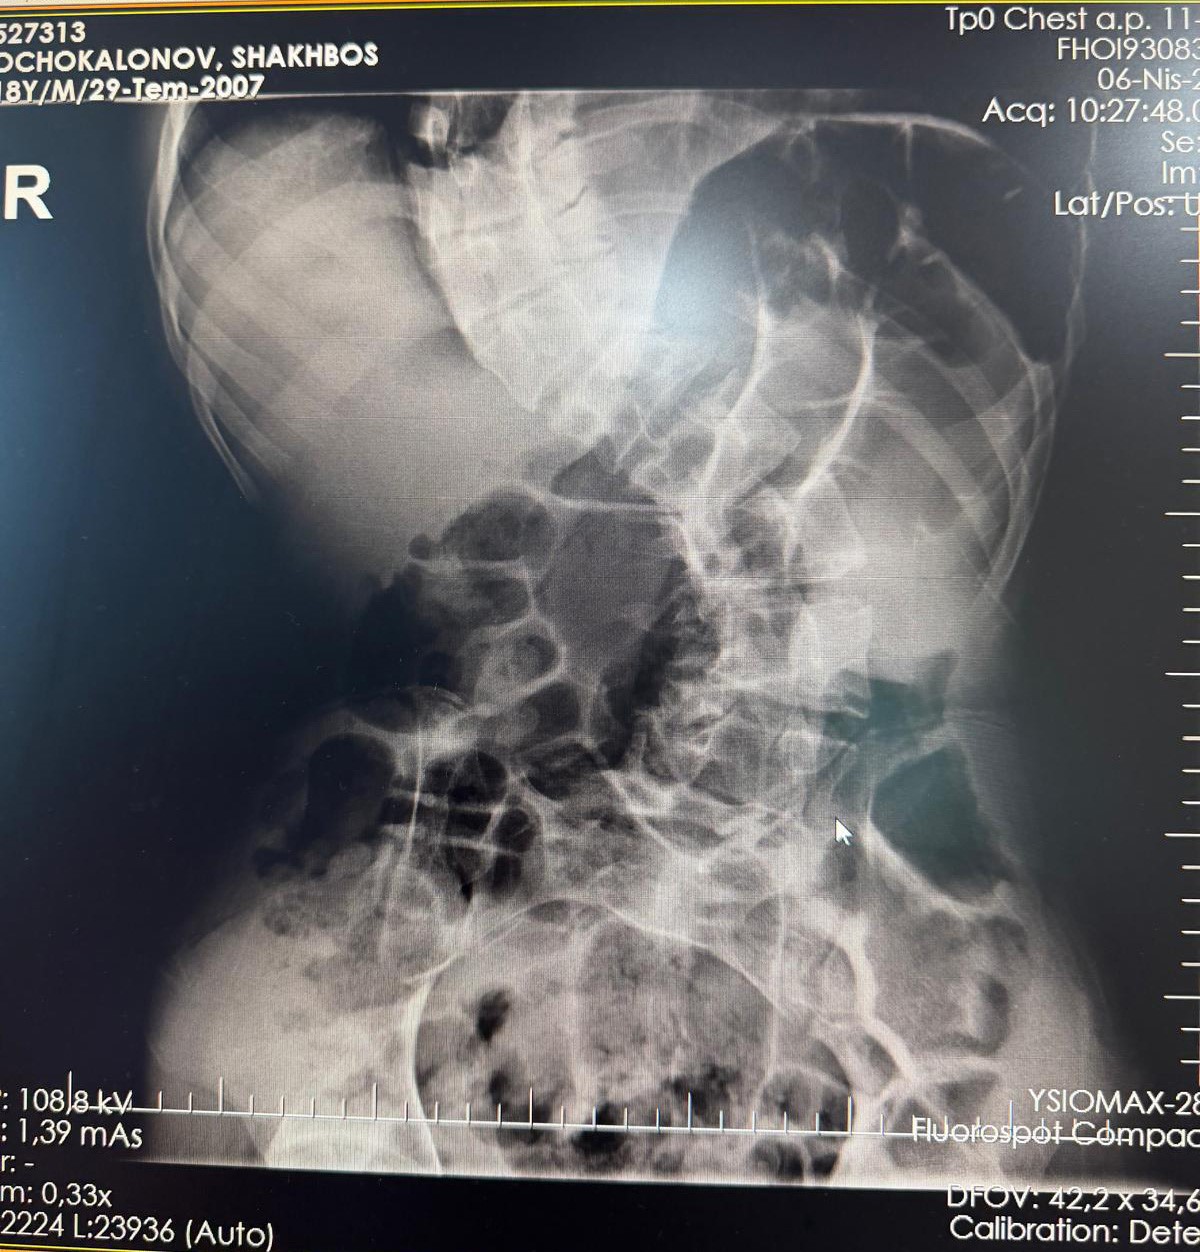

Başarılı geçen ameliyat sonrası hastanın yaşam kalitesinin önemli ölçüde arttığını belirten Ortopedi ve Travmatoloji uzmanı Prof. Dr. Mehmet Atıf Erol Aksekili, skolyoz hakkında bilgi vererek, "Skolyoz kısaca omurganın S şeklini almasıdır. Ön-arka planda omurganın S şeklini almasını biz kısaca skolyoz diyoruz. Skolyoz en sık adolesan dediğimiz ergenlik döneminde görülür. Ancak diğer hastalıklarla birlikte görüldüğünde daha ileri seviyelerde karşımıza çıkabilir. Hastamız 18 yaşında bize başvurdu. Nöromüsküler skolyoz dediğimiz, nörolojik hastalıkların eşlik ettiği bir skolyoz tipi mevcut. Bu skolyozlar erken yaşta ortaya çıkar ve daha hızlı ilerler. Bu yüzden hastamız bize 90 dereceden daha ileri bir seviyede başvurdu" dedi.

Erken teşhis edilmesi halinde daha az cerrahi ile daha iyi sonuç alınabileceğini belirten Aksekili, "Skolyoz erken tanındığında fizik tedavi, egzersiz ve korseleme gibi yöntemlerle ilerlemesini kontrol altına alabiliyoruz. Hastamızda ileri skolyoz olduğu için iki aşamalı cerrahi uygulandı. İlk aşamada Halo Femoral traksiyon yöntemiyle skolyoz kısmen düzeltildi. İkinci aşamada ise vidalar, rodlar ve osteotomi ile omurga düzeltildi" diye konuştu.